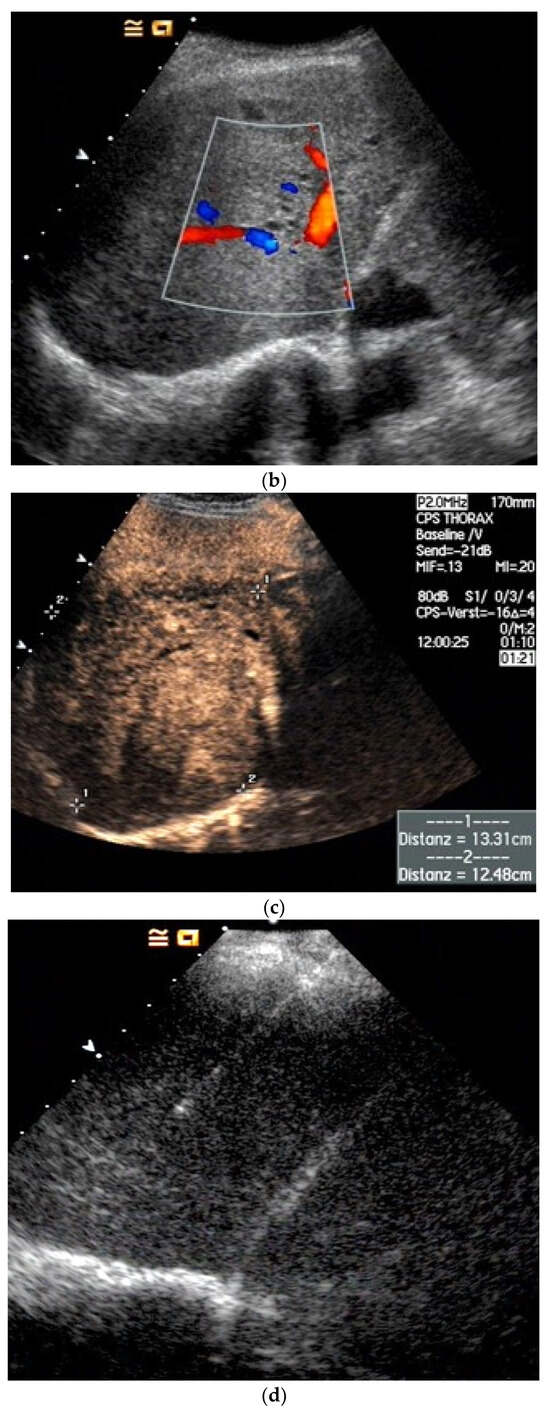

| Splenosis | Round, homogeneous lesions. Macrovessels on CDI are possible. Spleen-typical contrast behavior in CEUS with long-lasting contrast enhancement over several minutes. |